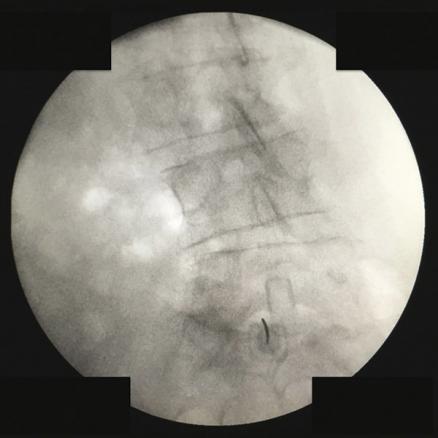

Abord interlamaire L5 sous fluoroscopie

2. Abord interlamaire L5 sous fluoroscopie